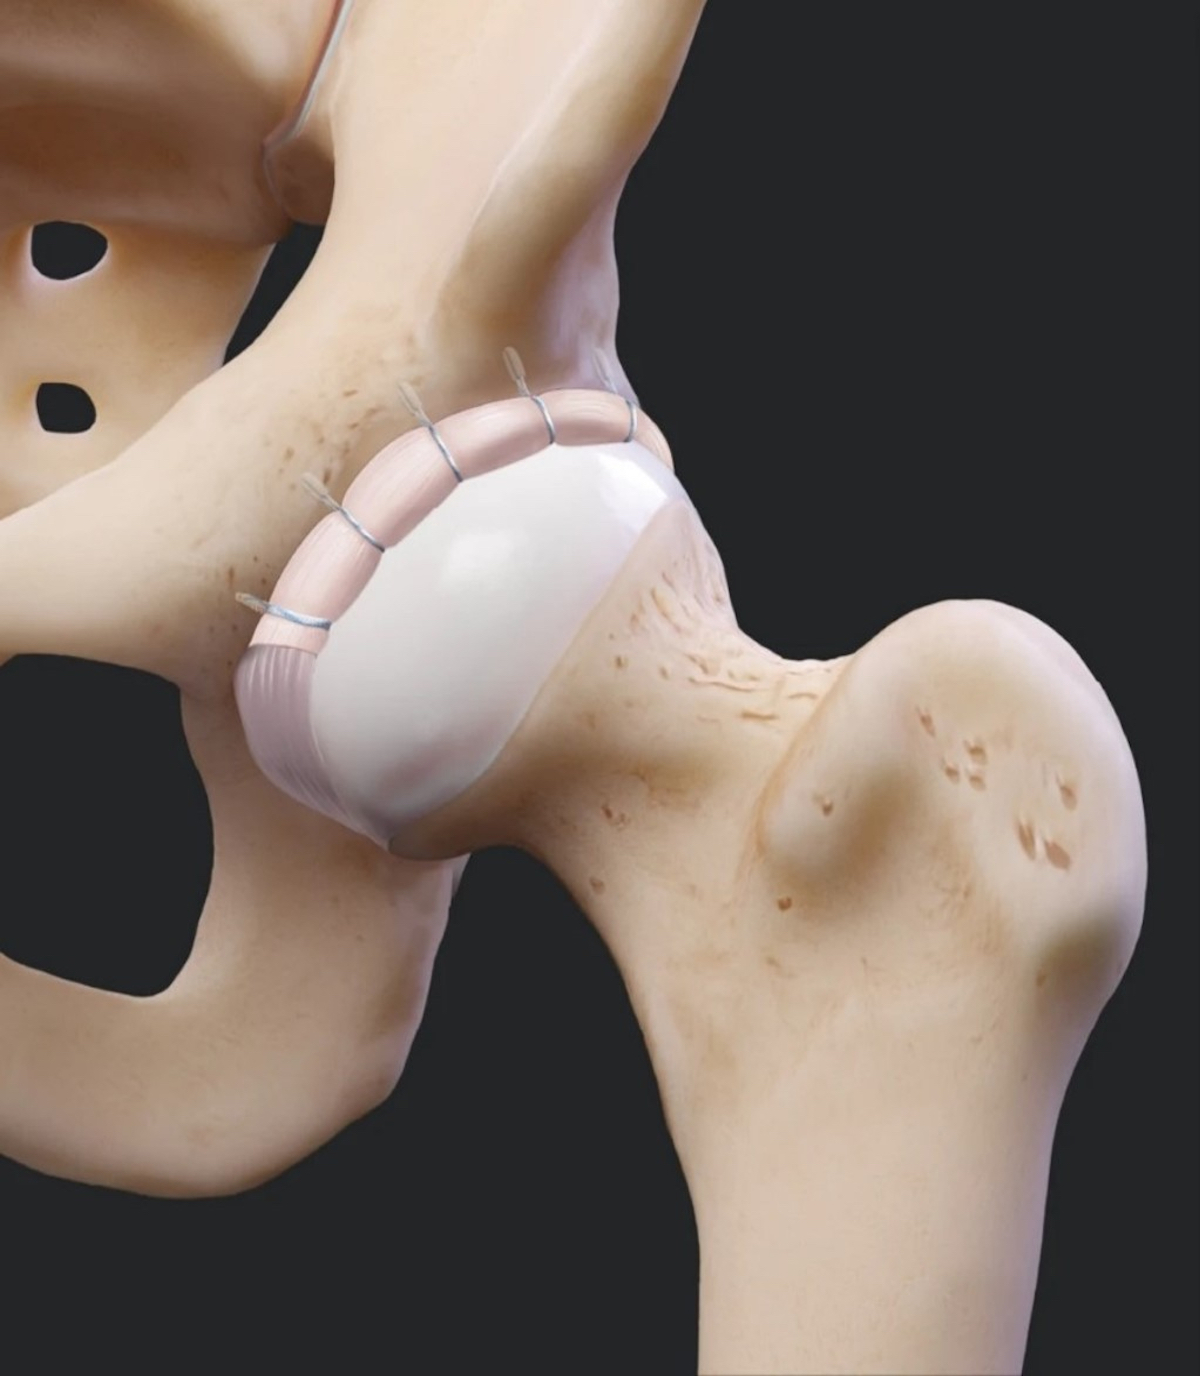

- Danno iniziale con lesione del labbro acetabolare: artroscopia dell’anca con riparazione del labbro acetabolare (Fig.3)

- Danno moderato con alterazione irreparabile del labbro: Artroscopia dell’anca con shaving selettivo del labbro o Trapianto segmentale del Labbro (Fig. 4)